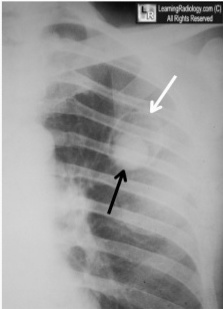

Crescent sign and halo sign = invasive aspergillosis

Solid mass surrounded by radiolucent crescent